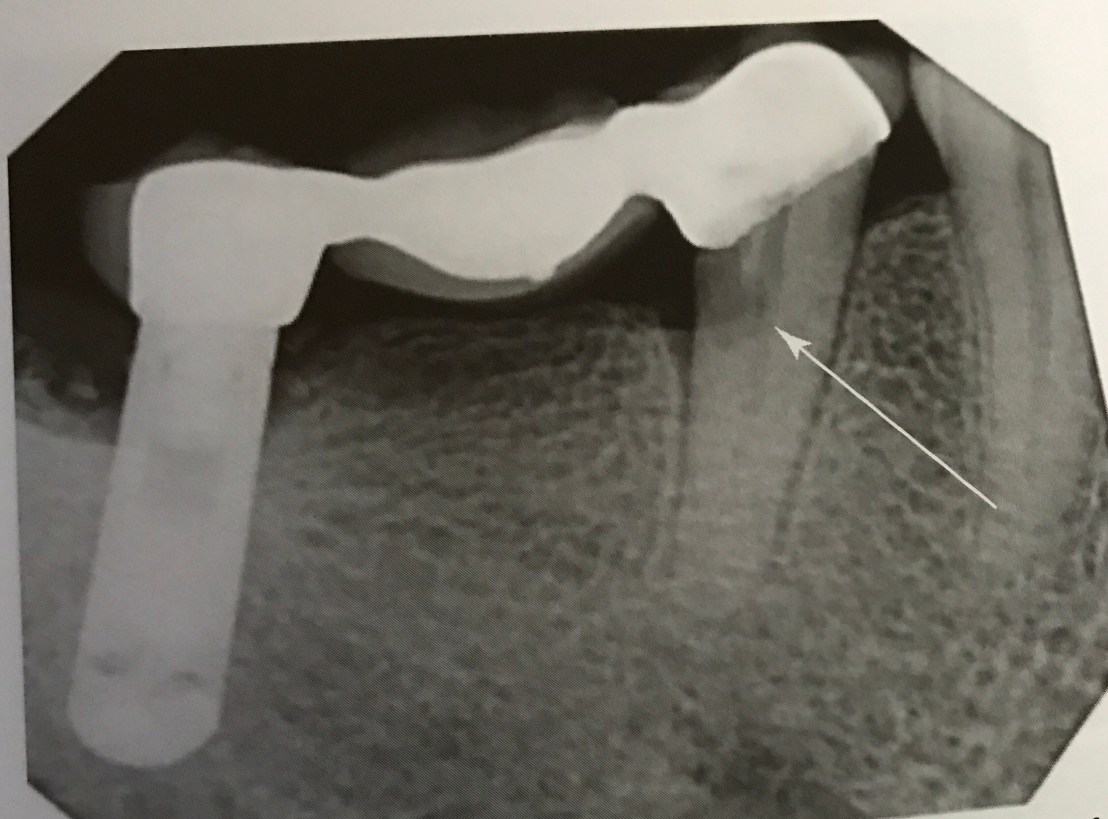

อันนี้ผมเพิ่งเคยเห็น น่ากลัวมาก คือ ฝังไปโดน Sublingual artery ครับ

อันตรายของมันคือ เกิด Sublingual hematoma ไป obstruct Airway

สังเกตฟิลม์ OPG ระดับ Implant อยู่ต่ำกว่า CEJ ของฟันข้างเคียงมาก ปลายของ Implant จึงทะลุ Lingual plate ไปโดน Artery

ในรูป D การใช้ Forceps ดึงลิ้นคนไข้ออกมาเพื่อ stop bleed และเปิด Airway รอทีม EMS มาถึงครับ

รูป Gross แสดง Artery ที่เกี่ยวข้อง และ Film แสดงการ Perforate ชัดเจน

รูป D แสดงการใช้ Bimanual pressure เพื่อหยุด bleed โดยใช้นิ้วชี้กด Gauze ใต้ลิ้นและนิ้วโป้งกดจาก Extra-oral บริเวณใต้คางในทิศดันขี้น